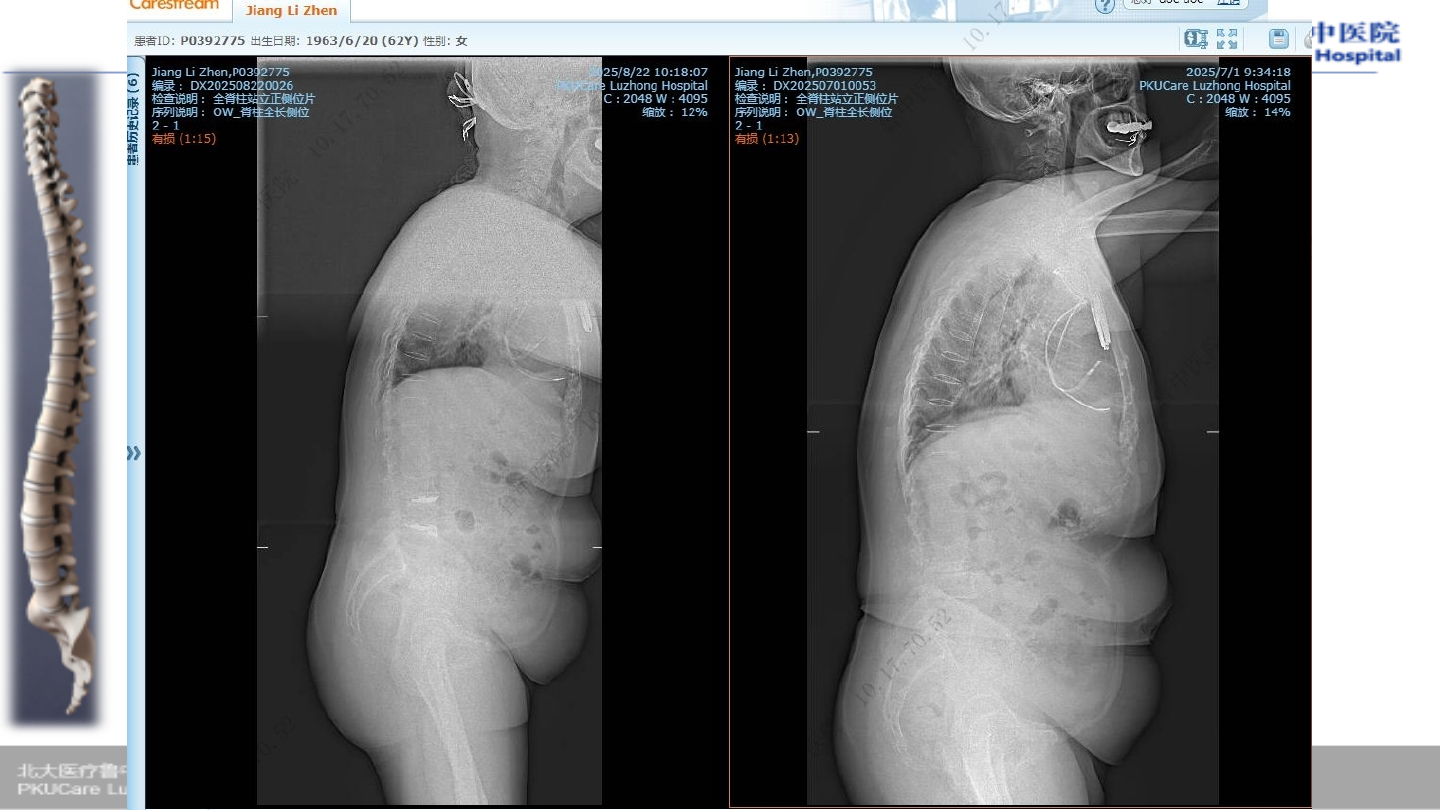

术前腰椎

X-ray

术前